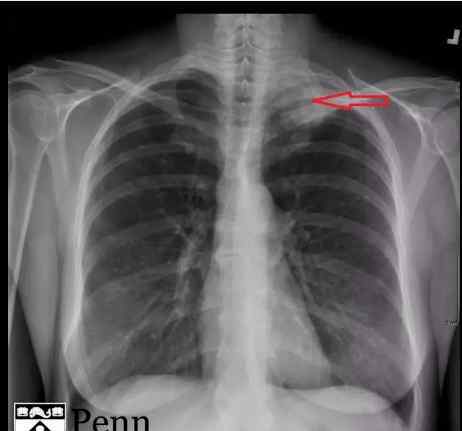

图1显示了胸片的前后位置,在左肺尖有高密度阴影(红色箭头)

胸片显示:左肺尖高密度影。

胸部平片:三分之二的患者可以在胸片上看到肺尖的高密度影。在一些患者的胸片上可以看到不对称的单侧(肺)尖帽。病变可能累及肋骨或扩散至锁骨上窝。

CT:平片CT可以用来确认平片上的高密度影。此外,它还可以用于评估骨骼受累。平片对肺、胸膜、胸壁和上腹部肿瘤转移的诊断价值有限。增强CT对评估血管受累和淋巴结受累非常有用。

图1显示了胸片的前后位置,在左肺尖有高密度阴影(红色箭头)

胸片显示:左肺尖高密度影。